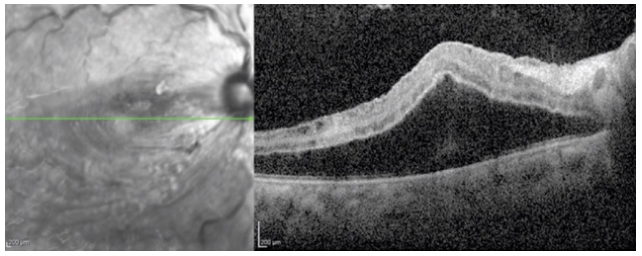

A 23-year-old black woman was 27 weeks pregnant, her right eye vision decreased for 3 days, and she had obvious anemia in her previous history. Check that BVCA is 20/250 OD, 20/20 OS. There was no significant change in anterior segment examination and intraocular pressure. In the funduscopy, the change of the left eye was not obvious, and the funduscopy of the right eye showed venous dilatation with scattered flame like bleeding, cotton wool spots and purtscher spots around the lower nipple (Fig. 1). OCT showed retinal thickening, subretinal effusion and edema of nerve fiber layer (Fig. 2). The blood pressure was 174/122 due to delayed fluorescein angiography during pregnancy. In view of these findings, doctors diagnosed purtschers retinopathy and speculated that it might be caused by preeclampsia.

Figure 1 Fundus imaging of the right eye showed venous dilatation (a), cotton spots (b), hemorrhage (c) and purtscher spots (d); Left eye unaffected (E)

Figure 2 OCT showed retinal thickening, macular edema, subretinal effusion and edema of nerve fiber layer